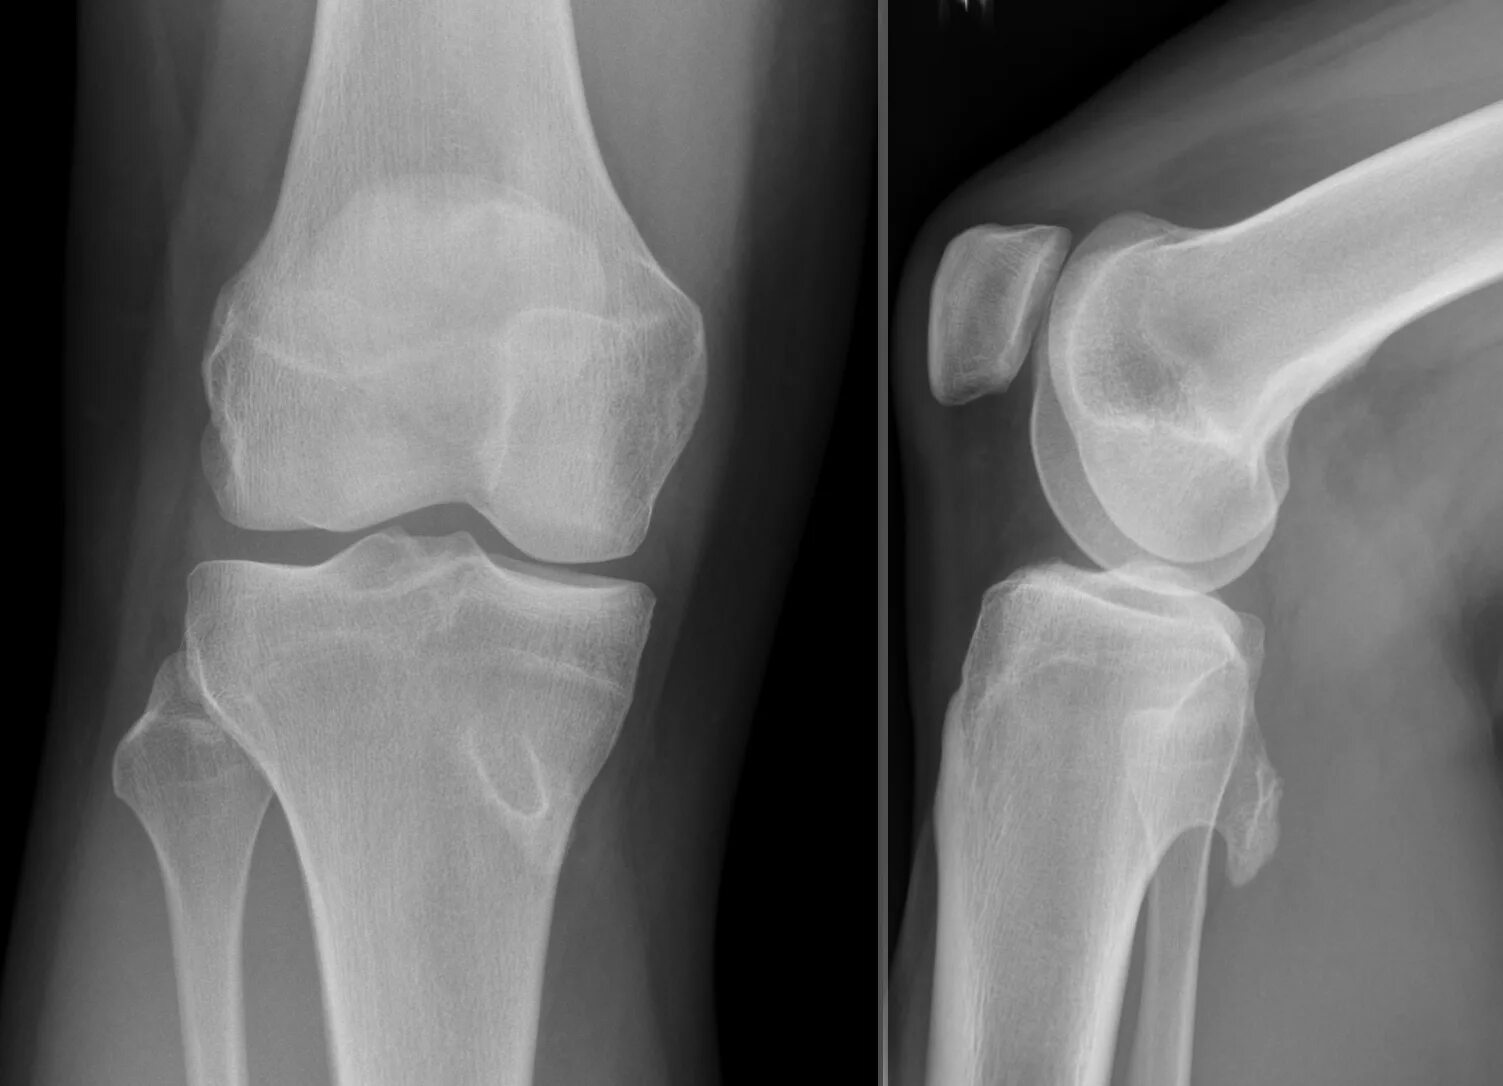

Экзостоз мкб 10